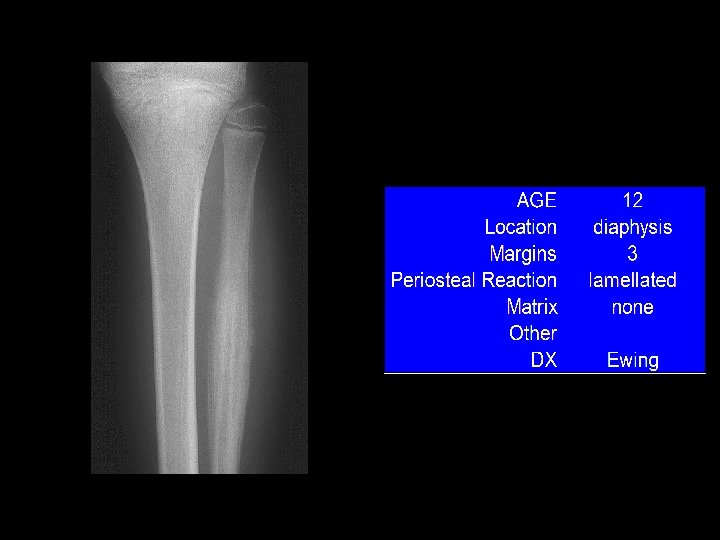

In case of Bone Tumors: look for Location! Age Age Behavior

Location and age of patient most important • parameters in classifying a primary bone tumor. Simple to determine from plain • radiographs.

Reaction of bone to tumor Limited responses of bone • destruction: lysis (lucency) reaction: sclerosis remodeling: periosteal reaction Rate of growth determines bone • response slow progression, sclerosis prevails – rapid progression, destruction prevails –

Example 9 “onion-skin”

Example 9 “onion-skin”